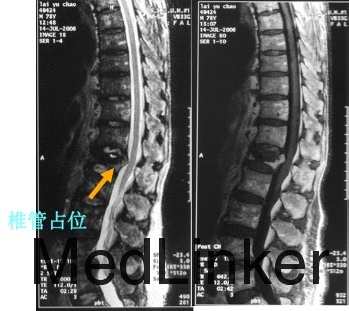

辅助检查:MRI检查示腰1椎体骨质疏松性压缩性骨折。

治疗:因患者椎体压缩骨折明显,椎体后缘骨折不完整,突入椎管,且硬膜囊受压,因此不适合行椎体成形术。给予单节段椎弓根钉固定并椎板切除减压术。骨折椎置钉结合钉道骨水泥加强稳定性。术后随访效果满意。